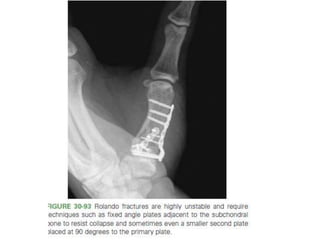

• Pilon fractures.

– Highly unstable,stifness of PIPJ.